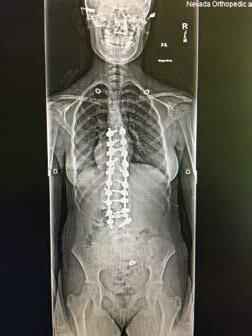

Dr. Yevgeniy Khavkin, the founder of Khavkin Clinic, was raised in Moscow, Russia. He was Inspired to go into the medical field by his mother, a pediatric surgeon, and started his exposure to medicine at age 14 by assisting his mother in surgeries.

Dr. Khavkin started medical school in Moscow when he was 16 and, after his family relocated to the US, transferred to medical school at the University of Chicago, where he also completed his neurosurgical training.

After finishing spine fellowship at Johns Hopkins University, Dr. Khavkin became the director of the neurosurgical spine program at Northwestern University before moving to Las Vegas in 2010. One of only a few fellowship trained spine neurosurgeons in Las Vegas, Dr. Khavkin pioneered a number of spine surgery techniques and was the first surgeon in Nevada to perform complex spine oncological procedures such as sacrectomies and en bloc spondylectomies.

Dr. Khavkin: Khavkin Clinic is a multispecialty practice that includes Las Vegas Neck and Back, Las Vegas Sinus and Las Vegas Headache. We pride ourselves on the comprehensive approach to the diagnosis and treatment of the diseases of the nervous system and the spine.

Even though my expertise is in spine surgery, most of our patients fortunately do not require any surgical treatment and we guide them down the non-surgical path to make sure they get better and return to the pain free life.